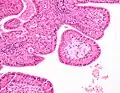

Cytopathology of Warthin's tumor, with typical cellular features (and a relatively uncommon binucleated cell).[1] Pap stain. | |

The appearance of this tumor under the microscope is unique. There are cystic spaces surrounded by two uniform rows of oncocytes, which are epithelial cells with abundant, granular, eosinophilic cytoplasm.[7] The cystic spaces have epithelium referred to as papillary infoldings that protrude into them. Additionally, the epithelium has lymphoid stroma with germinal center formation.